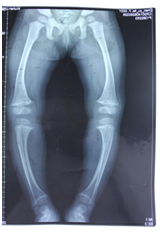

何女士3年前生下大女儿,因为遗传关系,孩子一出生就被诊断患有低血磷性抗维生素D佝偻病,导致孩子双下肢骨骼弯曲,畸形明显。没有哪个母亲希望孩子重复自己的悲剧,多方求医问药后,终于在孩子2岁时,何女士带着孩子找到武汉济世矫形专家,经临床诊断,告知何女士,孩子小是矫治的最佳时期,完全可以通过矫形器来矫正孩子弯曲的双腿。考虑到在达到矫治畸形目的的同时,也要不影响孩子的日常生活,专家为孩子特别设计了两套矫形器。白天用日用型支架,穿戴上,不影响孩子走路;晚上则用夜用型矫形器,从而使孩子的下肢“O”型畸形得到了有效矫治。女儿坚持佩戴了一年,复查后畸形明显改善。又坚持二年继续矫正治疗,孩子的O型腿不见了,双腿之间原来的膝间距离足足有12公分,现在几乎没有了,双腿可以合拢,行走跑跳和普通孩子一样。